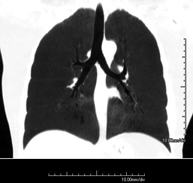

Prova diagnòstica que consisteix en l'estudi de les artèries pulmonars mitjançant l'ús d'un equip de TC (Tomografia Computeritzada) per obtenir imatges bi i tridimensionals. En aquest estudi és imprescindible l'ús de contrast iodat que permet una millor definició anatòmica. Aquesta prova està principalment indicada en els casos de sospita de tromboembòlia pulmonar (TEP) per descartar o confirmar la presència de coàguls sanguinis a l'interior de les artèries. - TC Tòrax d'alta resolució

Prova diagnòstica que consisteix en l'estudi del pulmó mitjançant l'ús d'un equip de TC (Tomografia Computeritzada) per obtenir imatges bi i tridimensional que permeten un estudi anatòmic altament específic del pulmó per poder valorar les estructures anatòmiques de petites dimensions. És una tècnica molt important en l'estudi dels pacients amb sospita de malaltia pulmonar. - TC d'estern